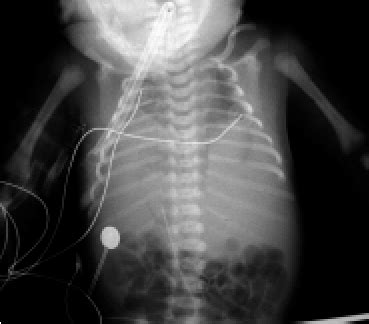

Thus, the term hyper rather than normal aeration is used. Web what does it mean? Web hyper aeration usually means that the lungs are expanded and have more air than one would expect. Web a pleural effusion is a collection of fluid in the space between your chest wall and lungs. What causes fluid build in lungs? Web respiratory failure results from inadequate gas exchange by the respiratory system, meaning that the arterial oxygen, carbon dioxide, or both cannot be kept at normal. Web it means that there is an abnormal increase in lung volume with an increased filling of alveoli. The lungs are hypoerated with increased interstitium that could be due to hypoaeration. The reticulogranular pattern is more prominent and uniformly distributed than usual. Web moderately severe respiratory distress syndrome (rds).

Hypopnea is overly shallow breathing or an abnormally low respiratory rate. Thus, the term hyper rather than normal aeration is used. Alan faustino answered internal medicine 28 years experience inflammation:. Ask an expert medical questions what does it mean?. This type of lung is seen in people affected with copd (chronic. Web a pleural effusion is a collection of fluid in the space between your chest wall and lungs. Web moderately severe respiratory distress syndrome (rds). Web i know that hypo means below or less than and that aeration has to do with breathing in air. The lungs are hypoerated with increased interstitium that could be due to hypoaeration. But what causes hypoaeration and is it significant in any way?. Hyperaeration or hyperinflation is sometimes used to describe the chest xrays of patients with obstuctive lung disease like copd or severe asthma.